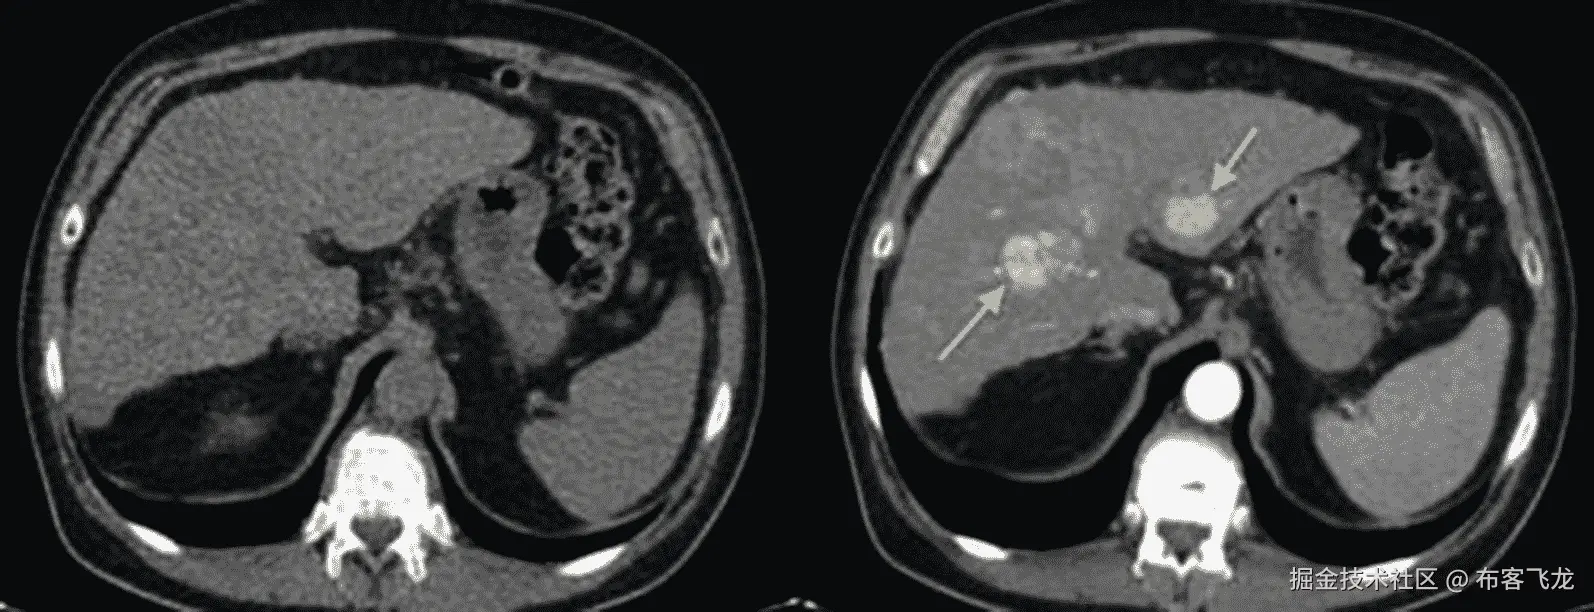

最后,不同的模式可以使用不同的造影剂来突出某些组织区域。由于不同组织对药物的吸收率不同,某些组织就显得特别突出。CT 成像使用碘基,而磁共振成像使用钆基,通常口服(如片剂)或静脉注射(直接泵入血流)。如图 8-5 所示,由于使用了对比剂,经过一段时间(20-30 秒延迟)后,您可以看到致癌结节在肝脏中突出显示。

img/502837_1_En_8_Fig5_HTML.jpg

图 8-5

造影剂突出某些组织区域